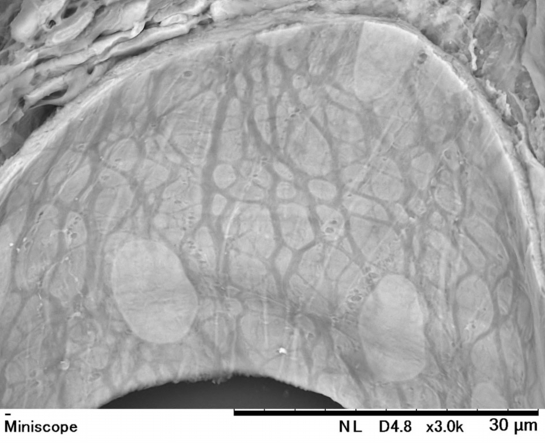

【 厚さ30 µm パラフィン切片の低真空走査型電子顕微鏡画像 】

Low-voltage scanning electron microscopic image of 30 µm-thick paraffin section

喉頭で観察された血管と内部を多う内皮細胞